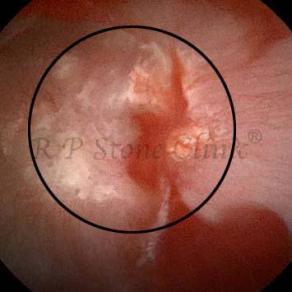

Kidney stone is a solid mass of CRYSTALS. It is the process of crystallization which initiates the formation of kidney stones. This happens in nephrons or units of kidney. Once a small crystal is formed, it can both grow & unite with other crystals leading to the formation of small concretion which eventually forms a stone. Once these large crystals detach from the collecting ducts, the process of stone formation starts in the renal collecting system. A recurrent kidney stone former is advised to know a little bit about something known as Randall’s plaque. Alexander Randall discovered plaques on the renal papillae eight decades back based on examination of 1154 pairs of autopsied Kidneys. He described these renal papillary lesions as cream colored or milk patch areas composed of calcium phosphate & calcium carbonate. These plaques could act as NIDUS for formation of KIDNEY STONE. Calcium Oxalate stone can form on this nidus & then detaches from this plaque to become a free floating stone in the collecting system of kidney

These images are taken as snap shots from the video recording of RIRS Surgery done at our hospital. These are Randall’s Plaques seen with Digital FLEX XC & Digital FLEX XC S. The cream or whitish patches are seen on the tips of RENAL PAPILLAE as seen in images below.